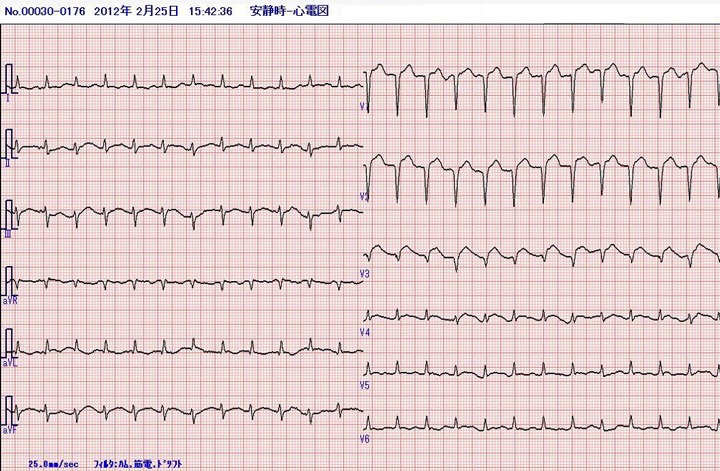

第7病日、午後3時半、突然の胸部苦痛を訴え、その際に記録されたのがこの心電図である。

全身の冷汗と呼吸困難感がある。SpO2は90%に低下。BP149/100mmHg、脈拍150/分。入院時の心電図を下段に示す。

第7病日の心電図

洞頻脈、V1-5でST上昇を認め、V1-3でQS patternを示している。左前下行枝における急性冠症候群、特に急性前壁中隔心筋梗塞を示唆する心電図である。至急に測定した心筋トロポニンTは10分で(+)、白血球数は600/mm3と増加していた。